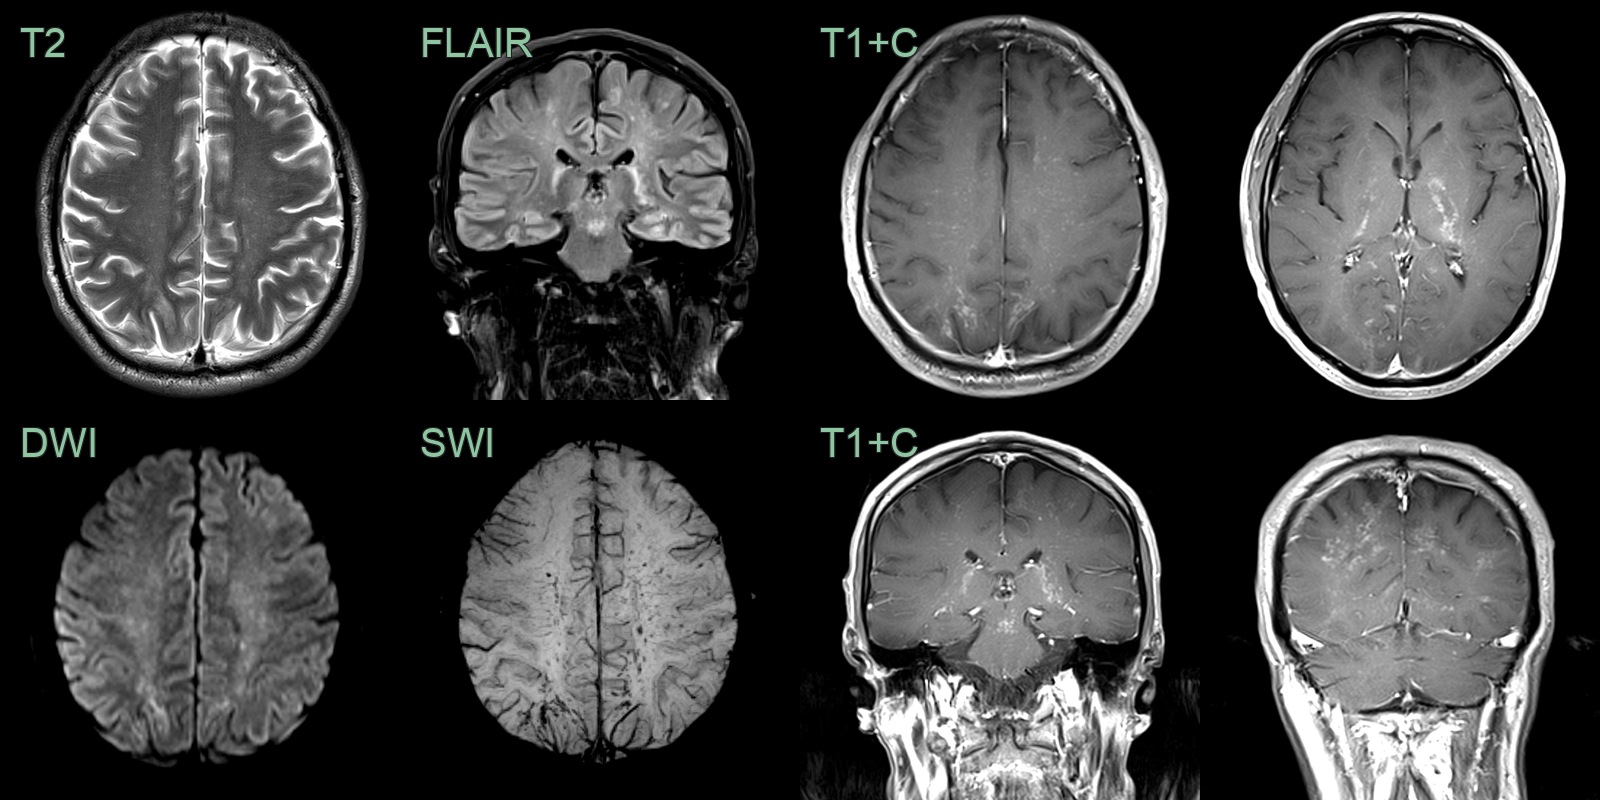

• 70-year-old patient with progressive right sided weakness.

• Patchy diffusion restriction and microhemorrhages in the centrum semiovale without contrast enhancement.